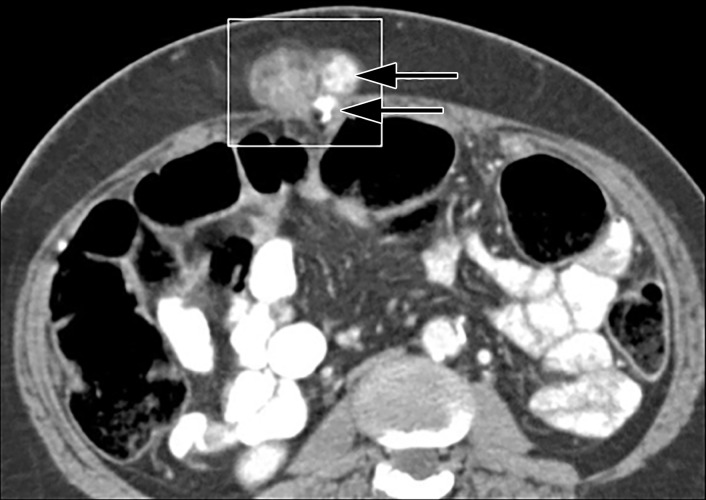

Figure 16a.

Desmoid tumors in a 34-year-old woman with Gardner syndrome and multiple palpable abdominal masses. Axial contrast-enhanced CT images show that the masses (black arrow) are centered in the underlying rectus abdominis muscles and have an appearance most consistent with that of desmoid tumors. A gastric mass (white arrow in a) was later characterized as adenocarcinoma, and changes from prior colectomy are also noted (* in b).

Figure 16b.